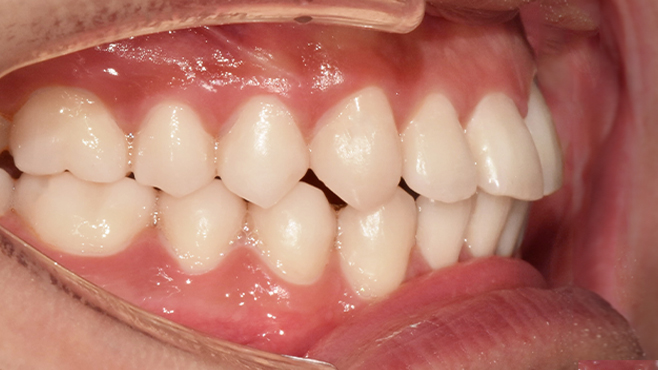

치과가 무서워 10년 동안 미뤄온 임플란트 수술 그 결과는?

2026.01.21